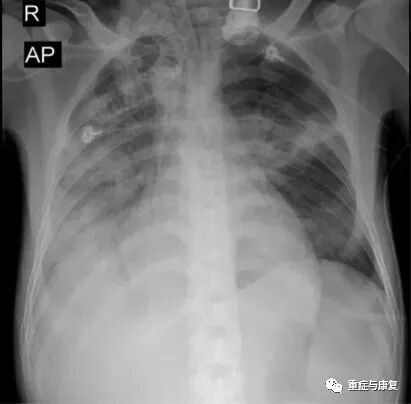

患者病情继续加重,次日出现深昏迷,全身皮肤巩膜深度黄染,复查肝功能:TBIL 518.4umol/L,DBIL 267.9umol/L,ALT 143U/L,AST 151U/L,ALP 118U/L;血氨:93umol/L;血气分析示OI 122。即进行血浆置换治疗,共4次(5/6-8/6),神志转清,胆红素水平较前明显下降,血氨下降。06-12因患者气促明显,PCT明显上升,并出现皮疹,考虑肺部感染进展,且不排除药疹可能,抗感染方案调整为美平、利奈唑胺、米卡芬净,继续积极的综合治疗,患者病情有好转,热退,肺部感染、肝功能不全逐渐好转,血氧改善,2015-06-17复查肝功能基本降至正常(TBIL 29.7umol/L,DBIL 12.1umol/L,ALT 38U/L,AST 40U/L),床边照片及胸部CT均提示肺部炎症明显吸收(图1-2,图1-4);于6-20成功脱离呼吸机拔除气管插管。

图1-2 床边照片(复查,2015-6-17)